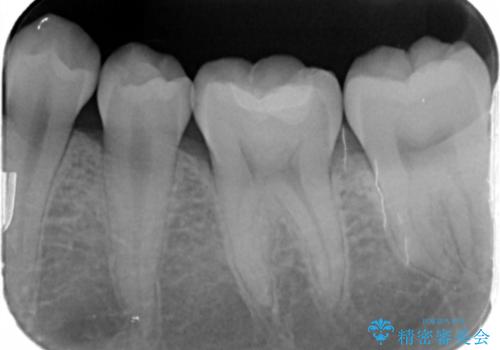

- 奥歯が黒いのが気になるとのことで来院。

レントゲンを確認したところ虫歯が大きくないので、以下の治療の提案を行った。

①虫歯を除去し、CR(レジン樹脂)で埋める。

安価で一日で終わり歯質を削る量が少ないが劣化しやすい(着色しやすい)。

虫歯の再発リスクが高い。

②虫歯を除去し、e-maxインレーで治療する。

歯質を削る量がCRで治療するより多く、また来院回数も多くなる(2回)。

劣化しにくく、虫歯の再発リスクが少ない。

コストがかかる。

患者様と相談し、虫歯が小さい段階で再発リスクの少ない治療を行いたい。

劣化も避けたいとのご希望だった。

そのため②のe-maxインレーでの治療の方針になった。